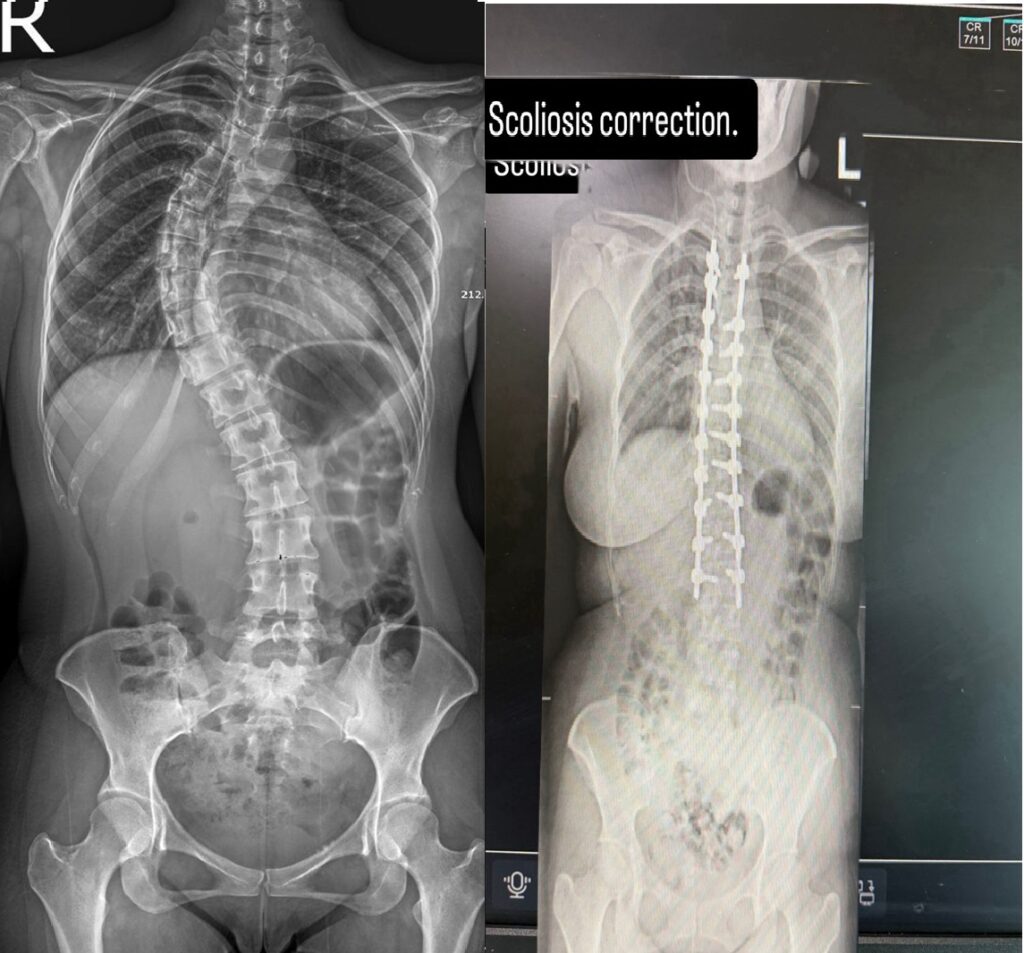

حقق مركز جراحة العمود الفقري في مستشفى السعودي الألماني دبي إنجازاً طبياً متقدماً، بعد نجاحه في إجراء واحدة من أدق وأعقد عمليات تصحيح اعوجاج العمود الفقري (الجنف) لمريضة عانت منذ طفولتها من تشوّه حاد ومهمل، تطوّر على مدى ثلاثة عقود إلى تيبّس هيكلي كامل في الفقرات، ما تسبب في آلام مزمنة وقيود حركية أثّرت بشكل مباشر على جودة حياتها.

ولم تكن الحالة مجرد إجراء تقويمي تقليدي، بل مثّلت تحدياً طبياً بالغ الدقة، نظراً لتحوّل الاعوجاج المزمن إلى تشوّه صلب في بنية العمود الفقري، ما جعل أي تدخل جراحي محفوفاً بالمخاطر ويتطلب خبرات تخصصية عالية وتخطيطاً دقيقاً وفق أفضل الممارسات الجراحية العالمية. وبقيادة البروفيسور حازم فريد، استشاري جراحة العمود الفقري، تم تنفيذ بروتوكول جراحي متقدم نجح في فكّ التيبّس الهيكلي وإعادة التوازن الطبيعي لمحور الجسم.

حيث اعتمد الفريق الجراحي خلال العملية، التي استغرقت نحو ثلاث ساعات ونصف، على تقنية القصّ العظمي (Osteotomy) لتحرير الفقرات المتصلبة وإعادة بنائها بدقة عالية. ولضمان سلامة النخاع الشوكي، جرى توظيف نظام متطور للمراقبة العصبية الفورية (Neuromonitoring)، الذي وفّر قراءة لحظية للإشارات العصبية طوال مراحل التصحيح، ما مكّن الفريق من العمل ضمن أعلى مستويات الأمان الجراحي.

وأسفر التدخل الجراحي عن نتائج فورية لافتة، حيث استعادت المريضة استقامة قامتها وقدرتها على الوقوف والمشي بصورة طبيعية بعد ساعات قليلة من العملية، منهية رحلة طويلة من الألم والتيبّس والقيود الحركية. ولم يقتصر الأثر على التصحيح الجسدي فحسب، بل انعكس بشكل إيجابي على حالتها النفسية وقدرتها على العودة إلى ممارسة حياتها اليومية بثقة واستقلالية.